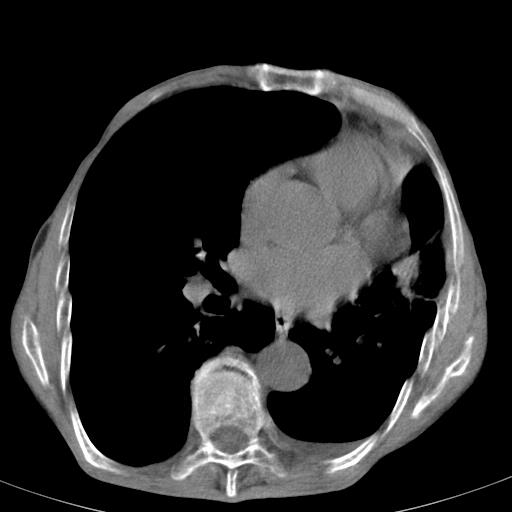

患者78岁,咳嗽胸闷一年余,近月来左侧胸痛;

建议强化,首先考虑左肺癌胸膜转移。

左侧少量胸腔积液,局限胸膜增厚,结合病史,考虑慢性肺炎.

患者左侧胸廓塌陷说明是长期病变,考虑tb性胸膜炎可能性大,另外有明显的肺气肿,建议行结核菌素实验,或者增强扫描

1.慢支肺气肿。2.左肺感染,建议治疗后复查。3.左侧少量胸水。

1)考虑左肺慢性感染性病变(结核可能)。2)左肺上叶周围型肺癌不排除;建议追踪复查。3)肺气肿。4)左侧胸腔积液,左侧胸膜增厚、粘连。